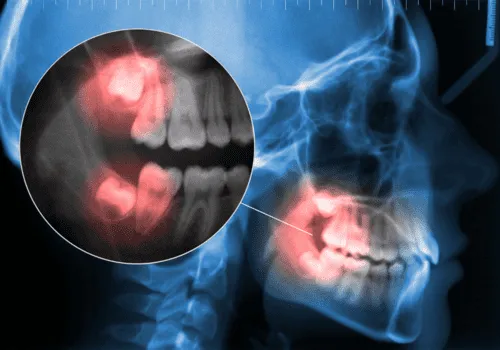

Na to vprašanje lahko odgovori le zobozdravnik. Rentgenski posnetki bodo pokazali, ali so se razvili, kako rastejo in ali je dovolj prostora zanje.